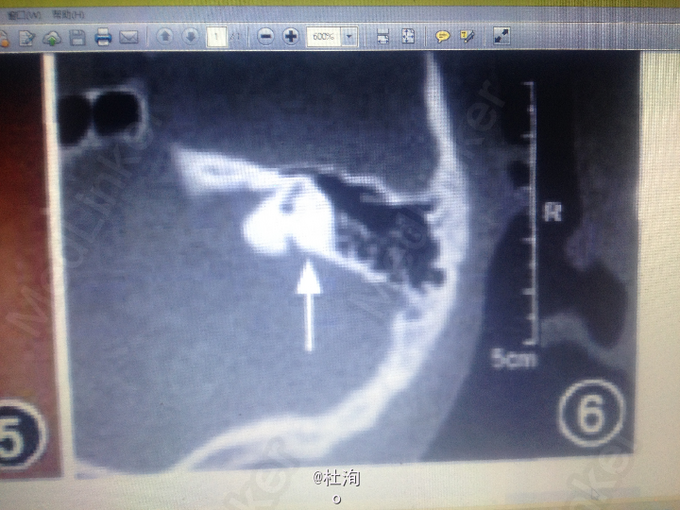

查体见:瘘管处挤压见清亮液体流出,患者的纯音测听检查结果:双耳中重度感觉神经性耳聋;耳部CT示:双侧前庭导水管扩大

诊断:鳃一耳-肾综合征 处理:建议行瘘管造影检查,明确瘘管所经位置,制定手术方案切除瘘管。

鳃耳肾综合征(BORS)是一种常染色体显性遗传病,因第一、二鳃弓发育异常、听力障碍、泌尿系统畸形而得名。人群中发病率约为1/40 000,而在聋哑儿童中发病率为2%。BORS的诊断标准包括听力损伤、耳部畸形、第二鳃弓瘘管或囊肿,耳前瘘管及肾脏异常,5项中符合两项且家族史阳性者或无家族史而符合以上3项者。患者及其母亲、舅舅均表现了BORS中的3个主要症状,然而其各自症状并不相同。本文摘自《中华口腔医学杂志》